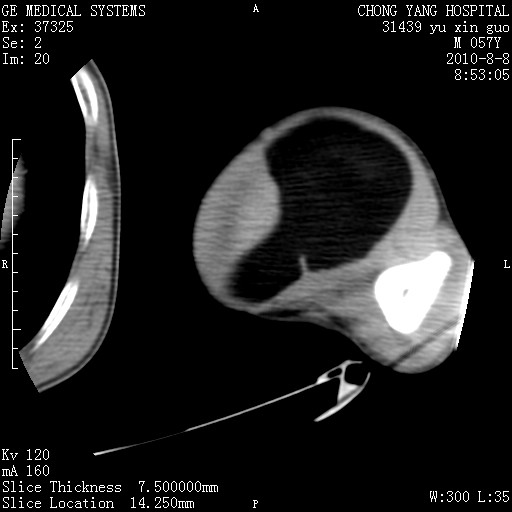

标题: CT28267:M57Y 上臂包块8年余。 [打印本页]

标题: CT28267:M57Y 上臂包块8年余。

上臂软组织内脂肪瘤。

软组织内脂肪瘤

包膜光滑、完整的脂肪密度肿块,支持脂肪瘤。